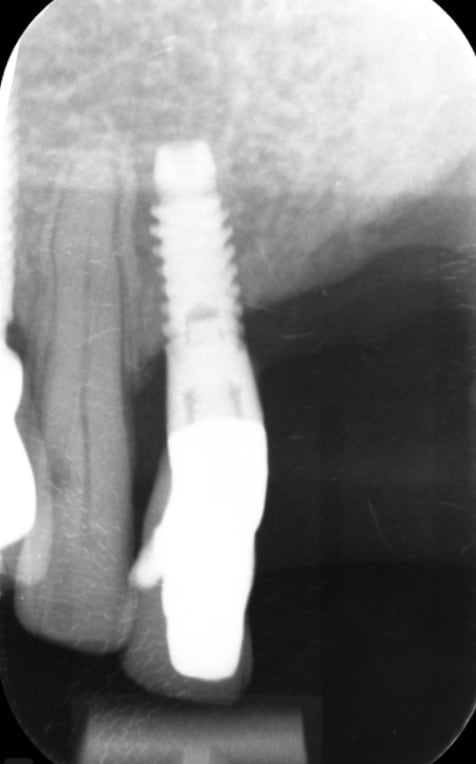

J'ai besoin d'aide pour identifier cet implant en 32 svp

un vieux microvent paragon/zimmer

https://osseosource.com/micro-vent-sd-3-25-paragon-/p-1360.html